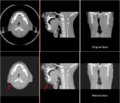

The project aims at allowing plan adaptation throughout the treatment course by means of CBCT. This imaging technique is at its early stage in radio– and proton-therapy application and it is not yet considered a reliable tool for planning. We would like to use Deformable registration algorithms and automatic segmentation for:

One crucial step of this approach is the rigid alignment prior to deformable registration. For CT/CBCT co-registration, this is even more difficult given the presence of immobilization devices (e.g. thermoplastic masks) and the different image quality.

A side problem includes the removal of the immobilization devices + tube artifacts from CBCT images. At the moment we proceed with a combination of registration and erode/dilate morphological operations given a contour on a previous image, but we would be happy to discuss about this :) (NB: maybe smt similar to the skull stripping algorithm would help us?)